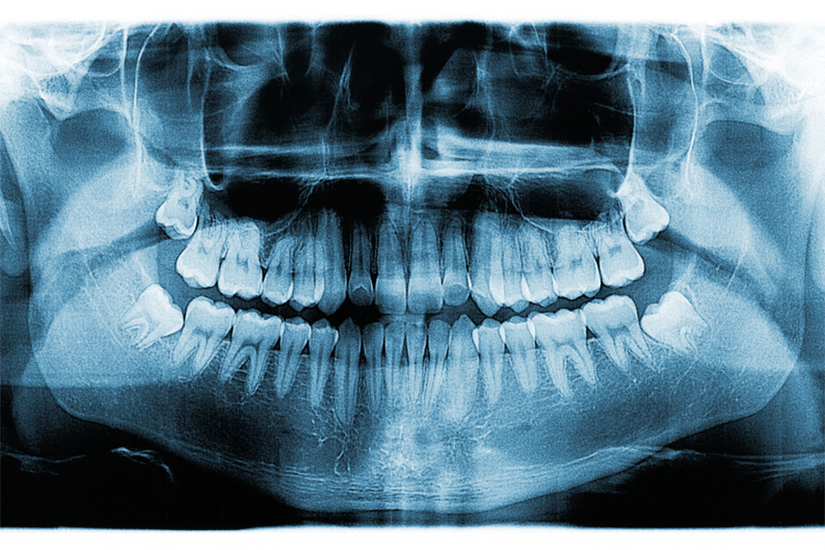

În 90% dintre cazuri, pentru evitarea problemelor, este necesară îndepărtarea tuturor molarilor de minte. Însă, fiecare caz este unic; astfel, tratamentul potrivit trebuie recomandat de către un medic stomatolog. Există situații în care medicii pot recomanda extracția uneia sau mai multor măsele de minte, drept tratament preventiv. În urma unei radiografii dentare, medicii pot vedea dacă poziționarea măselelor de minte reprezintă un motiv de îngrijorare.

Extracția măselelor de minte este indicată atunci când molarul este inclus, semiinclus, adică atunci când nu are suficient loc pe arcadă să erupă și să se poziționeze corect, într-o ocluzie stabilă.

Extracția molarului de minte inclus este o intervenție care implică mai multe beneficii decât riscuri. Înainte de procedură, medicul te va trimite să efectuezi o radiografie a cavității bucale și îți va cere informații despre tratamentele pe care le urmezi, astfel încât riscurile să fie cât mai bine gestionate. Ca în orice intervenție chirurgicală, există un mic risc de sângerare sau de infecție.